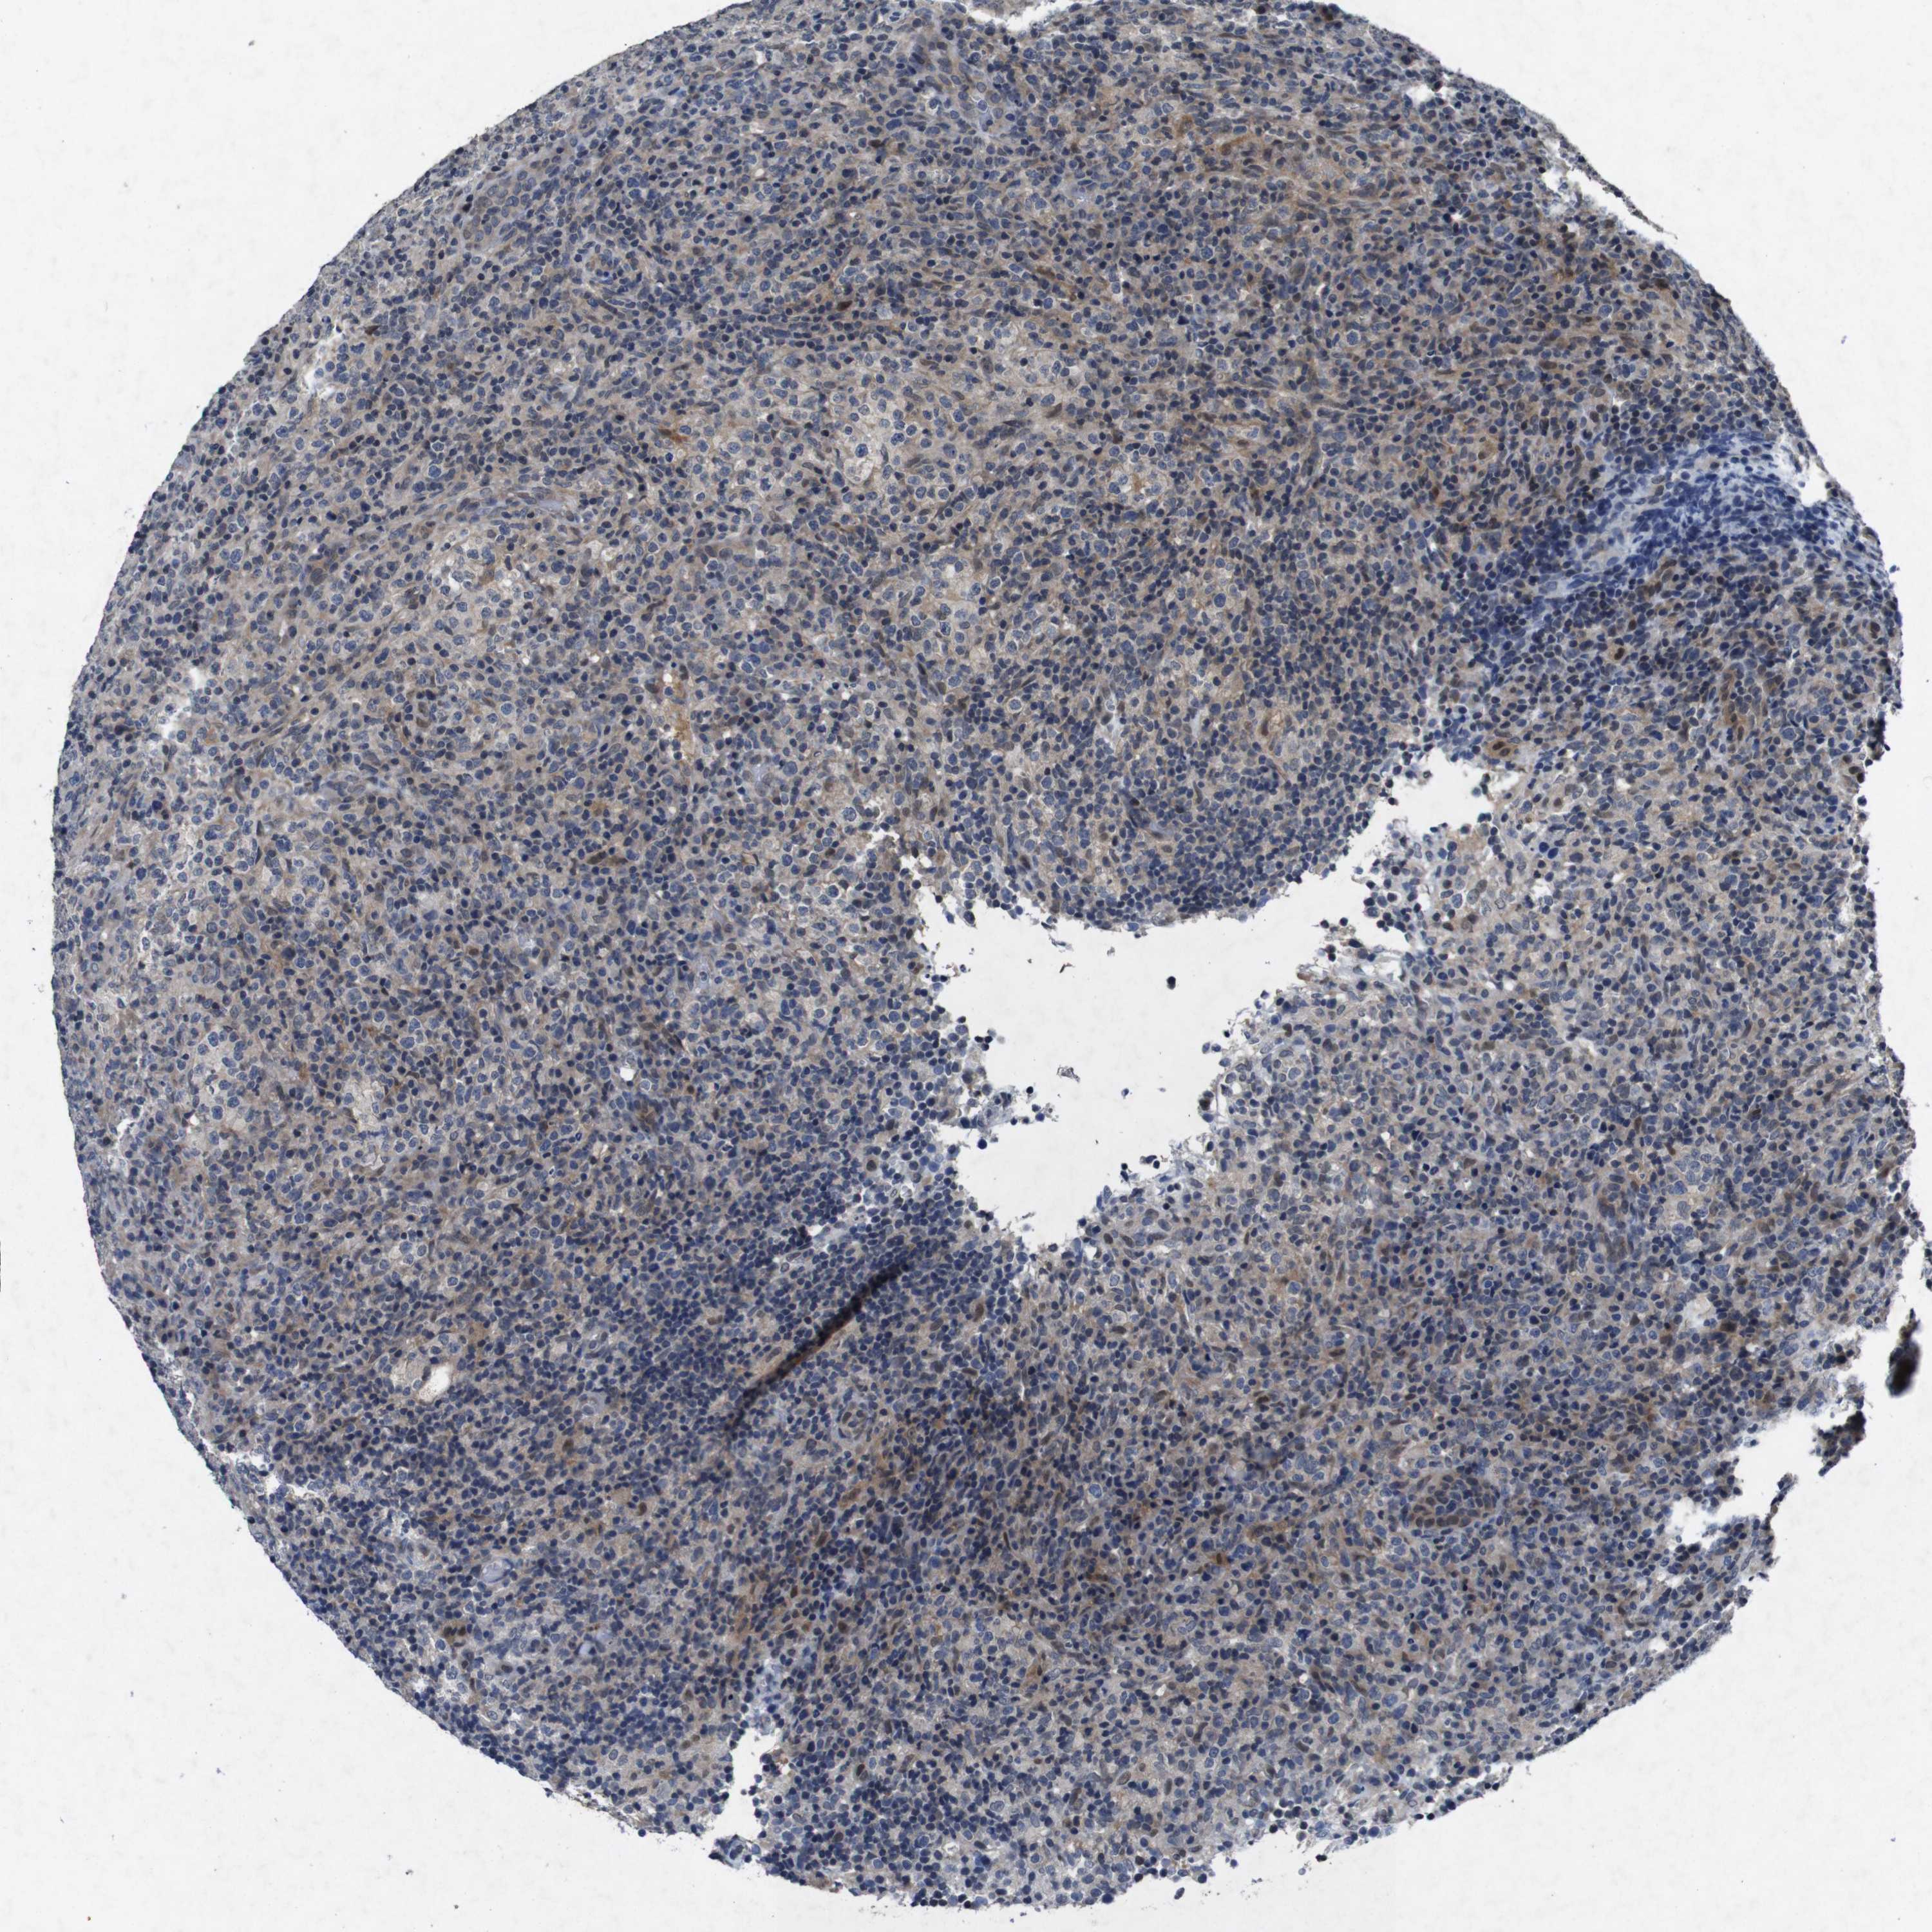

CANCER LYMPHOMA Show tissue menu

LYMPHOMA - Protein expressioni

A mouse-over function shows sample information and annotation data. Click on an image to view it in a full screen mode. Samples can be filtered based on level of antibody staining by selecting one or several of the following categories: high, medium, low and not detected. The assay and annotation is described here.

Antibody stainingi

Antibody staining in the annotated cell types in the current human tissue is reported as not detected, low, medium, or high, based on conventional immunohistochemistry profiling in selected tissues. This score is based on the combination of the staining intensity and fraction of stained cells.

Each image is clickable and will lead to virtual microscopy that enables deeper exploration of all samples and also displays staining intensity scores, fraction scores and subcellular localization as well as patient and tissue information for each sample.

Antibody HPA026441

Antibody CAB013090

Staining

High

Medium

Low

Not detected

Intensity

Strong

Moderate

Weak

Negative

Quantity

>75%

75%-25%

<25%

None

Location

Nuclear

Cytoplasmic/membranous

Cytoplasmic/membranous,nuclear

Hodgkin's disease, NOS

Malignant lymphoma, non-Hodgkin's type, High grade

Malignant lymphoma, non-Hodgkin's type, Low grade